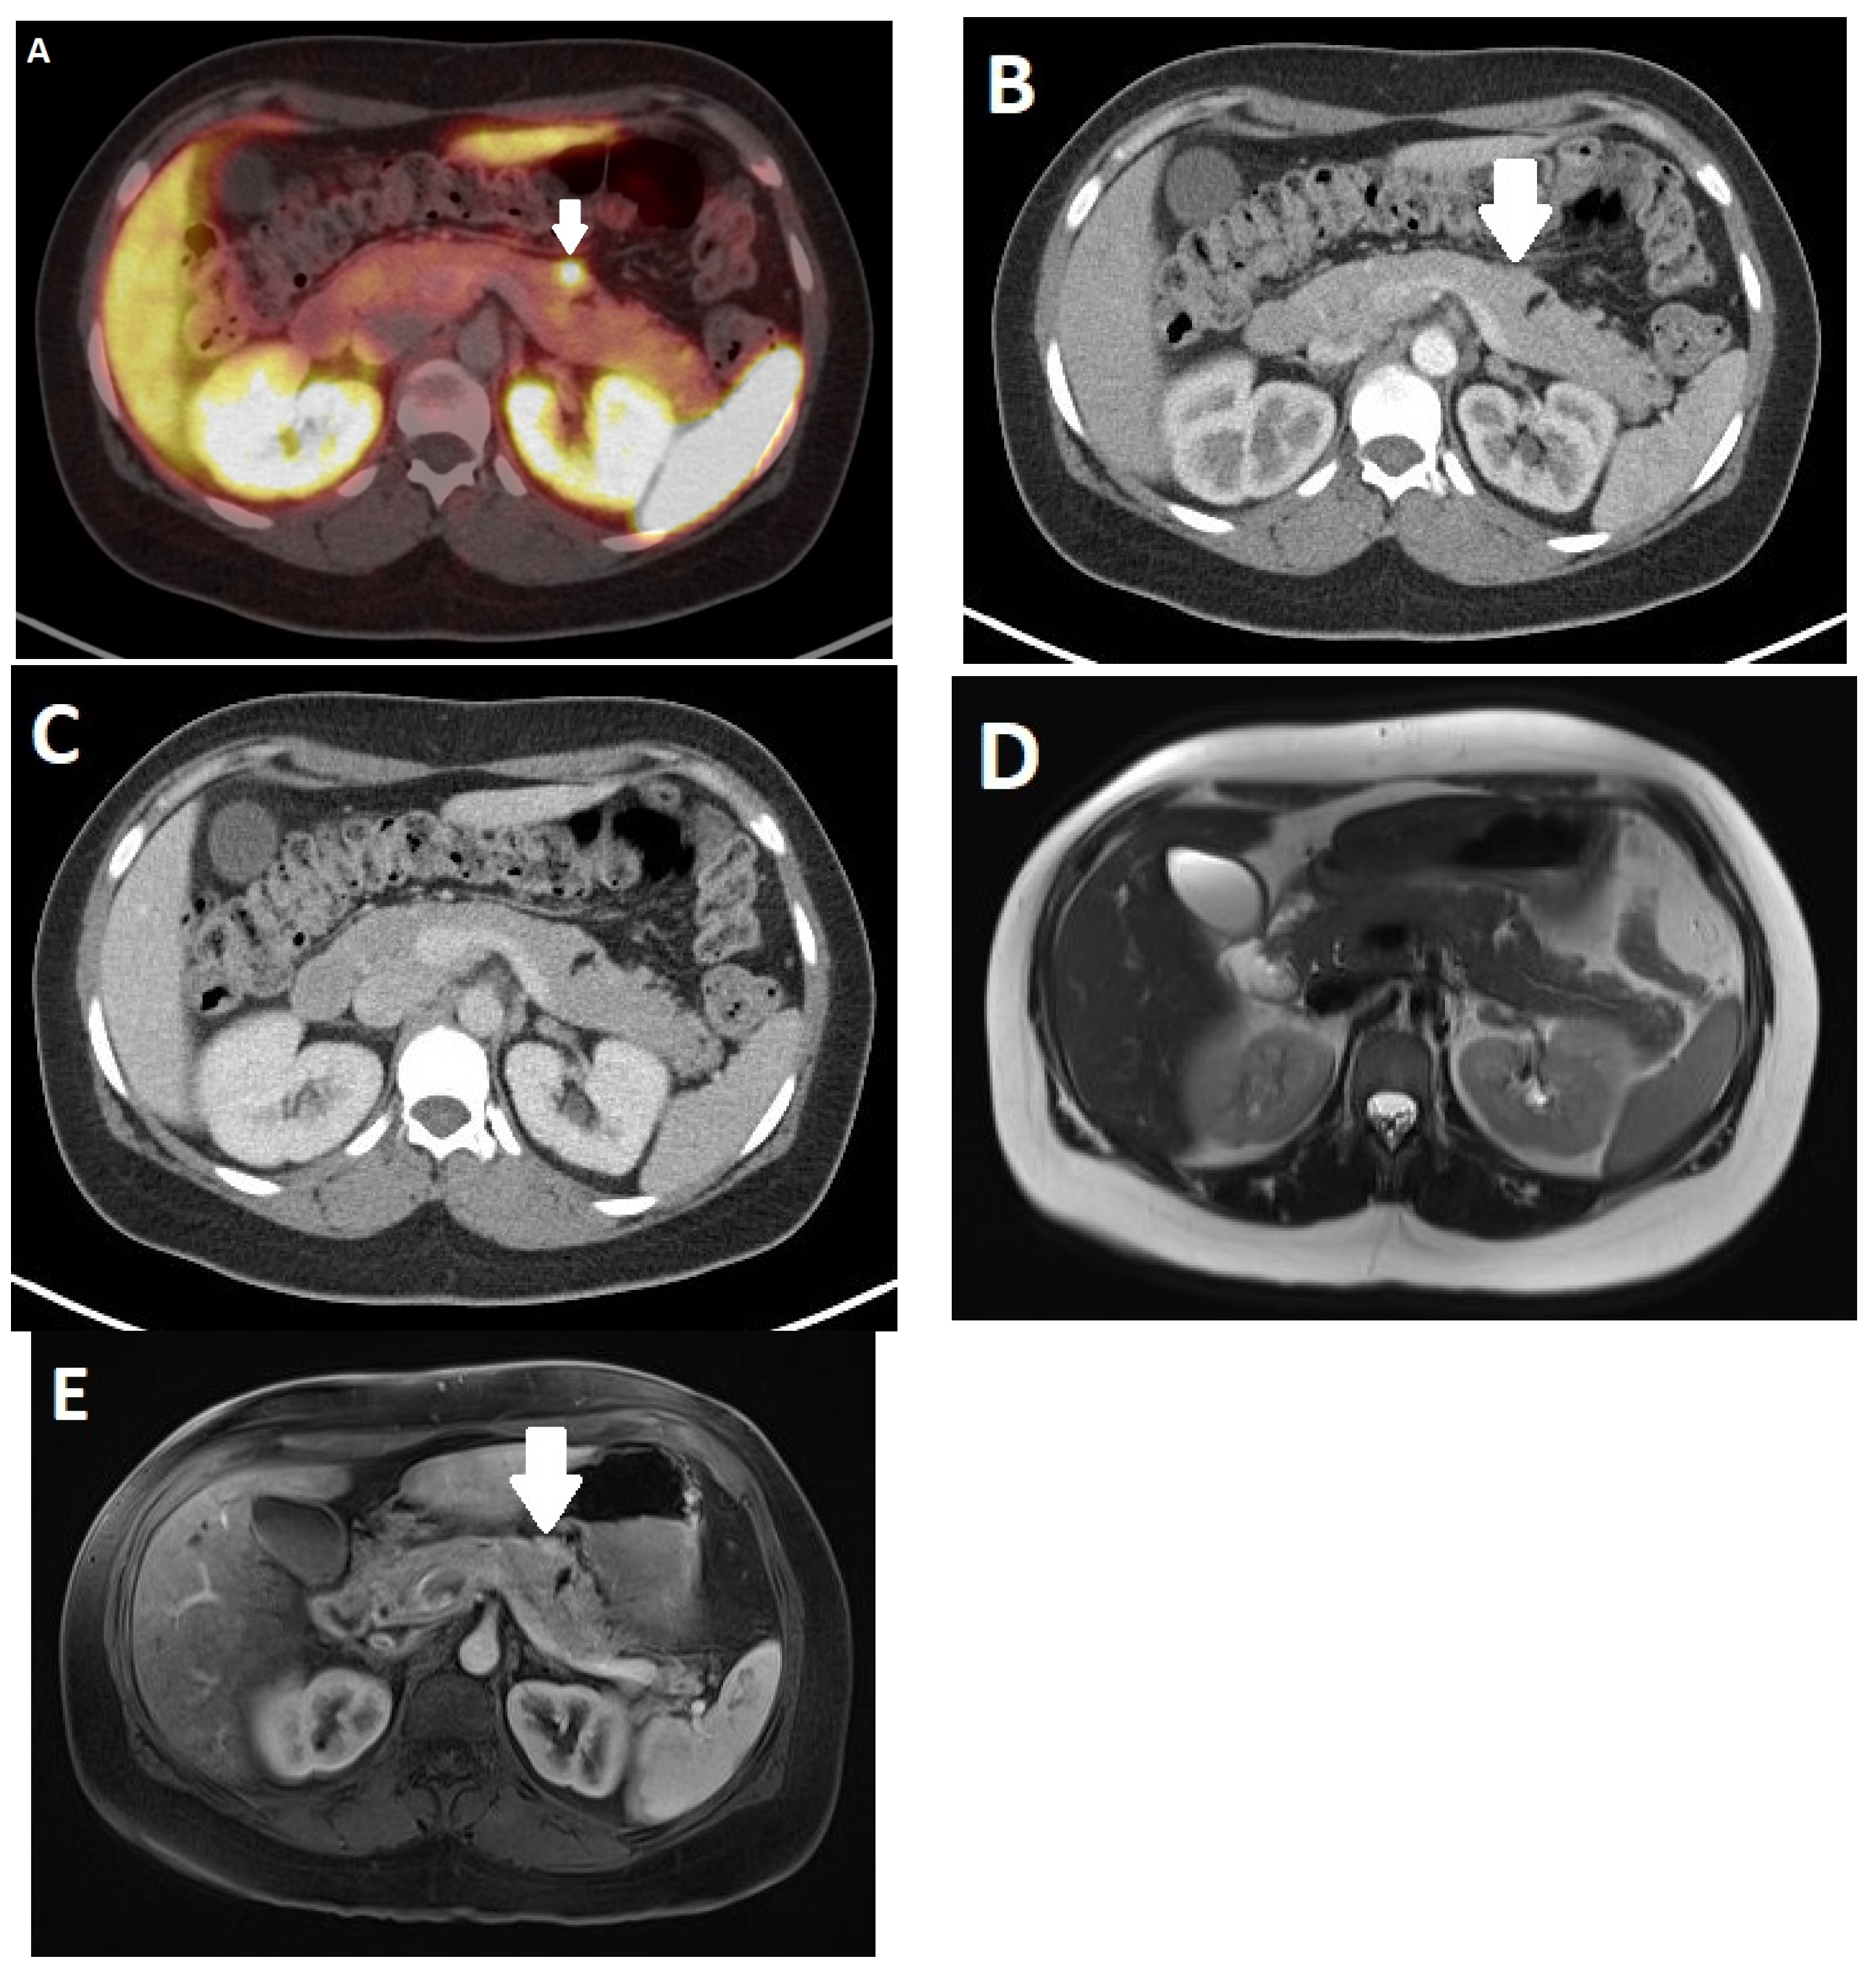

2.4. Imaging